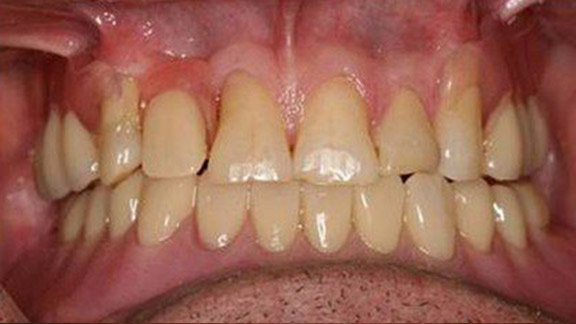

Crowns

Crowns Case 1

Crowns Case 2